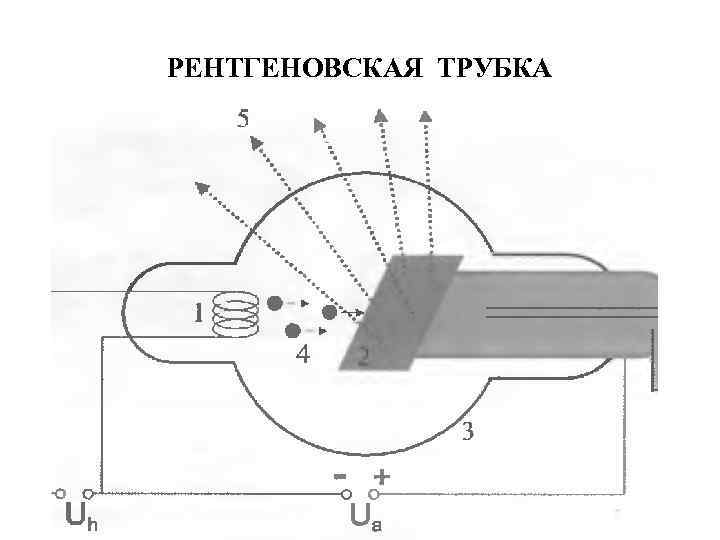

РЕНТГЕНОВСКАЯ ТРУБКА

РЕНТГЕНОВСКАЯ ТРУБКА